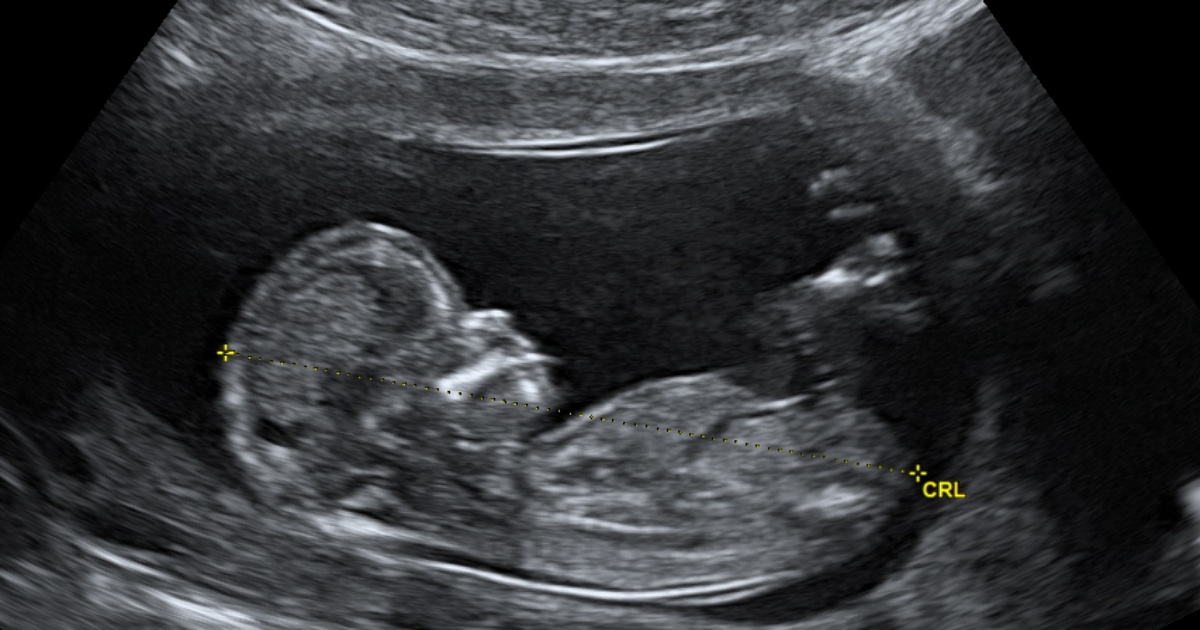

Определить пол 11 недель

Определить пол 11 недель 112 фото